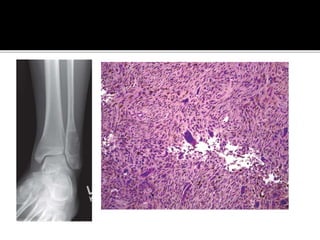

 Locally destructive, blood filled reactive

lesions of bone.

 Any bone. Most commonly proximal

humerus, distal femur, proximal tibia and

spine – 15% (posterior elements)

 Common in 1st-2nd decade, female

predominance.

 Presentation – Pain. Rapid growth can mimic

a malignancy. Spinal lesions – neurological

deficits.

 Radiology – Eccentric, expansile radiolucent

lesion, thin cortical shell. Fluid levels evident

on MRI

 Histology – Haemorrhagic cavernous spaces,

septae of fibroblasts, histiocytes,

haemosiderin laden macrophages and giant

cells.

 Solid variant of aneurysmal bone cyst – “giant

cell reparative granuloma”

 Surgical treatment – extended curretage and

grafting with a bone graft substitute under

tourniquet control.

 Spine/Pelvic lesions – Preoperative

embolization.

 Low dose radiation – associated with

malignant transformation.